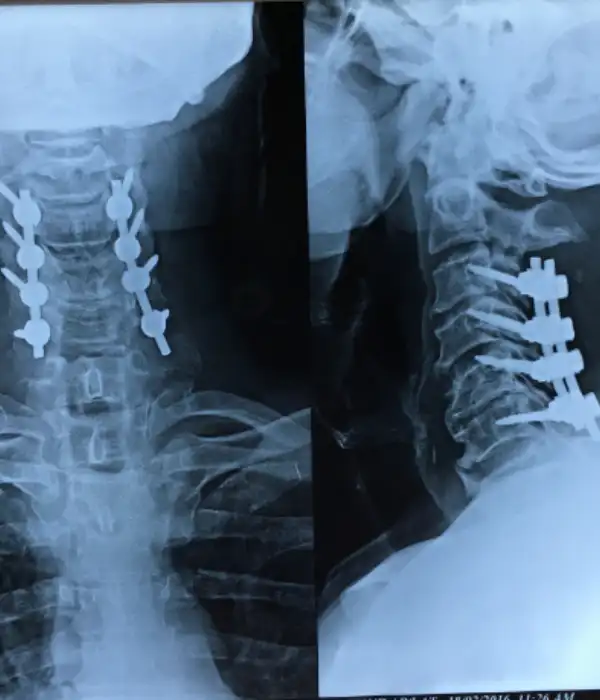

Minimally invasive C1-C2 fusion

C1-C2 instability Post OP X ray

C1-C2 fusion Post OP X ray

Instability in the atlanto-occipital joint results in hyper-mobility of the junction between the head and the neck which can cause severe pain or paralysis. It may result from rheumatoid arthritis or congenital defects that can accelerate degenerative arthropathy, resulting in spinal cord compression. At Kauvery Advanced Spine Centre, we use the latest developments in imaging, computer-assisted surgery, and instrumentation to provide safe surgery.